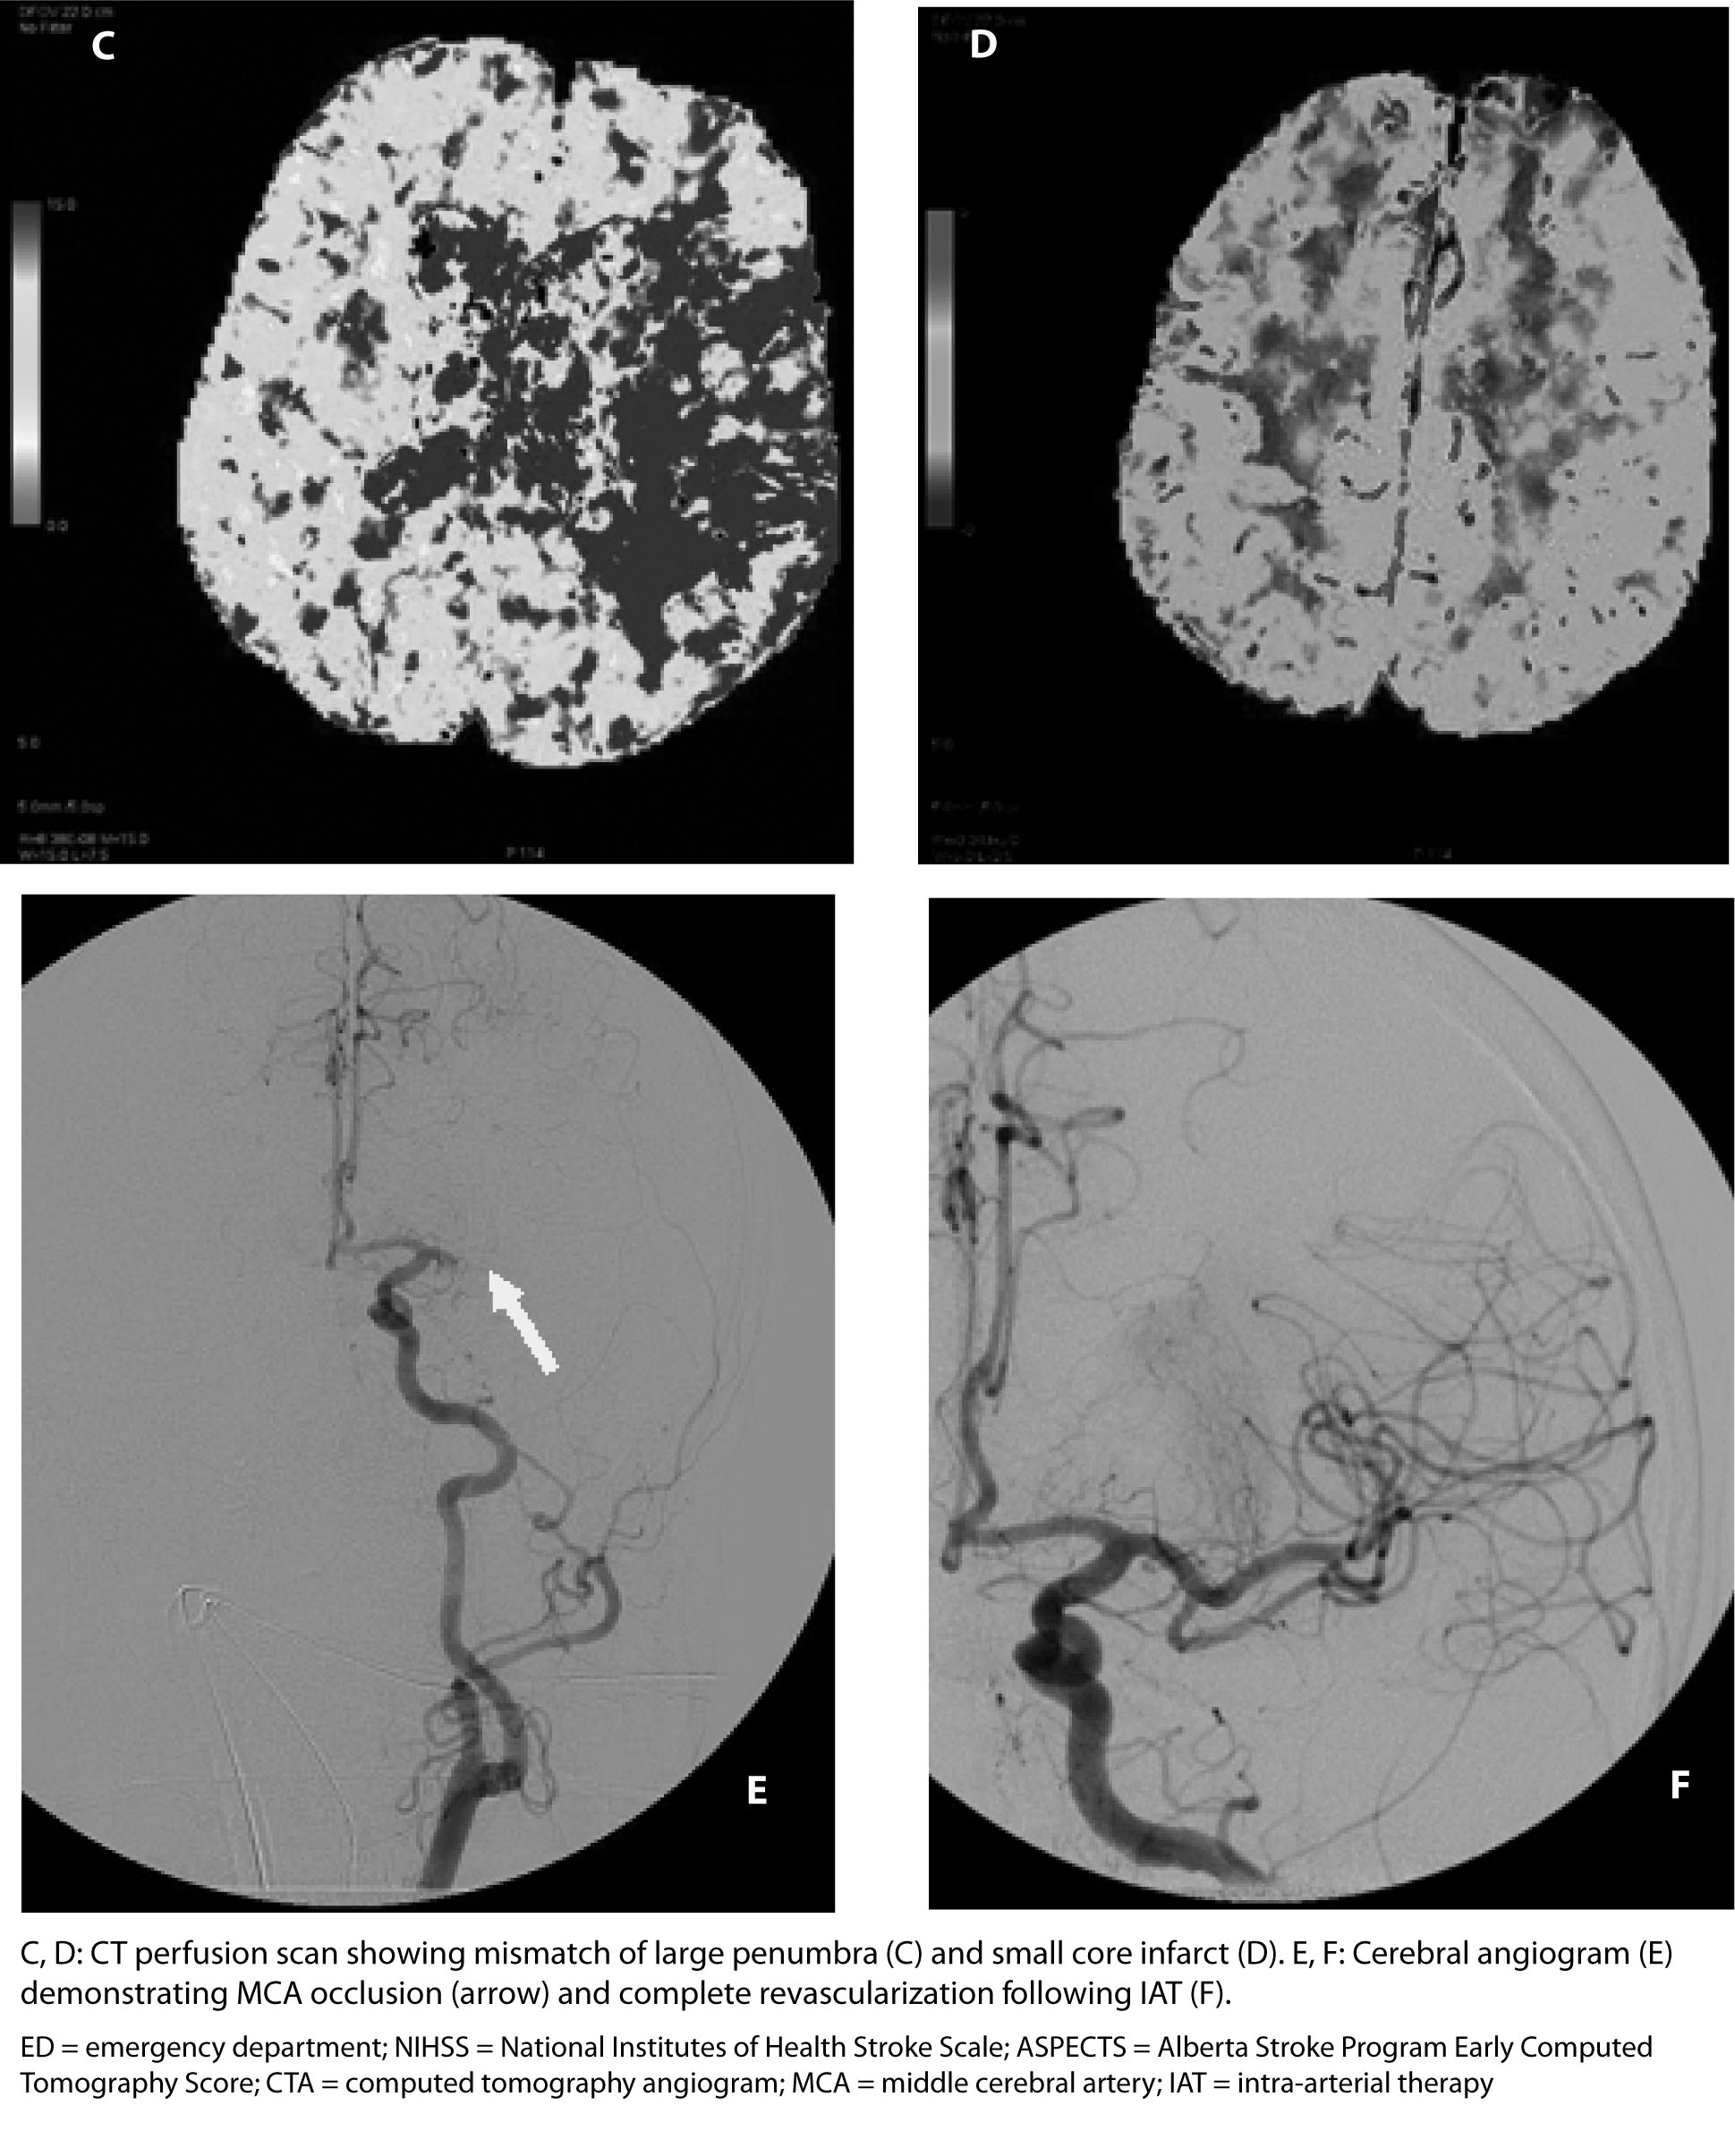

Diagnostic Workup of a Suspected LVO and IV-tPA as Bridging Therapy. The initial diagnostic evaluation of patients being considered for IAT should be similar to that performed on any stroke patient being considered for IV thrombolysis. (See Table 1 and Figure 1.) In fact, the vast majority of patients included in recent endovascular trials received IV-tPA in addition to intra-arterial treatment. The number of patients who first underwent IV thrombolysis prior to IAT ranged from 73-100% in these trials.45,47 IV-tPA remains an important method of therapy for patients with LVO for two reasons, ultimately demonstrating the significance of concurrent IV alteplase administration in eligible patients, even if they are planned for subsequent IAT.

Figure 1. Suggested Diagnostic and Treatment Algorithm for Patients with Acute Ischemic Stroke Due to a Large Vessel Occlusion

Once the decision to administer tPA is made, the patient next should undergo emergent noninvasive angiography to confirm the presence of an LVO, if suspected. (See Figure 1.) A high-quality CT angiogram (CTA) of the head and neck will provide data on the location of an intracranial LVO, the quality of collateralization, as well as the presence of comorbid extracranial carotid stenosis that may require concurrent intervention. Endovascular trials that did not require the confirmation of an LVO by CTA prior to randomization failed to demonstrate any benefit of endovascular treatment.54-56 If an acute occlusion of a proximal intracranial artery, such as the MCA or ICA, is discovered on angiography, then the patient may be a candidate for mechanical thrombectomy if there remains a large mismatch between ischemic penumbra (i.e., tissue at risk) and core infarct (i.e., established stroke). However, if there is a large area of established infarct, the patient is unlikely to benefit from intra-arterial intervention.52 The presence of core infarct can be determined through multiple techniques and has been used successfully to select patients for endovascular therapy through such modalities as noncontrast cranial CT,6,44 collateral scores on CTA,44,57 CT perfusion scans,45,46 and MRI.47,58 Often, the Alberta Stroke Program Early Computed Tomography Score (ASPECTS) is used to standardly quantify the amount of early ischemic changes in the MCA territory present on a noncontrast head CT.59 The ASPECTS scale is a 10-point, validated scoring system, where an initial score of 10 indicates a normal CT scan, and 1 point is subtracted for each abnormal area within 10 pre-specified regions of the cortex and deep subcortical structures. The higher the ASPECTS number, the smaller the core infarct, the larger the presumed ischemic penumbra, and the better the patient is a candidate for intervention. Many of the recent endovascular trials used a cutoff of 6 or better on the ASPECTS scale as part of the inclusionary criteria for trial selection, as these patients are thought to have the largest areas of salvageable brain tissue.44,46,47

Figure 2a. Neurovascular Imaging for an Acute Ischemic Stroke Patient Undergoing Evaluation for Endovascular Intervention |

|

Figure 2b. Neurovascular Imaging for an Acute Ischemic Stroke Patient Undergoing Evaluation for Endovascular Intervention |

![]() |